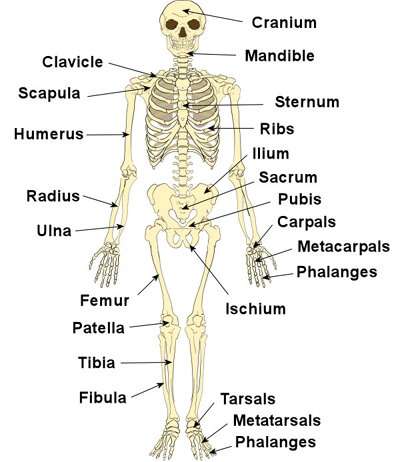

- Main bones of the skeletal system e.g. skull, humerus

MAIN BONES OF THE SKELETAL SYSTEM

The main bones of the skeletal system are:

1. Cranium (skull)

2. Orbit (eye)

3. Jaw bone

4. Cervical vertebra (neck bone)

5. Vertebral column

6. Scapula (shoulder blade)

7. Clavicle (collar bone)

8. Sternum (breast bone)

9. Ribs

10. Thoracic vertebra

11. Humerus (upper arm bone)

12. Radius and ulna (lower arm bone)

13. Carpals (wrist bone)

14. Phalanges (finger bones)

15. Femur (thigh bone)

16. Tibia and fibula (leg bones)

17. Patella (knee bone)

18. Tarsals (ankle bone)

19. Phalanges (toe bones)

MAIN BONES OF THE SKELETAL SYSTEM

The main bones of the skeletal system are:

1. Cranium (skull)

2. Orbit (eye)

3. Jaw bone

4. Cervical vertebra (neck bone)

5. Vertebral column

6. Scapula (shoulder blade)

7. Clavicle (collar bone)

8. Sternum (breast bone)

9. Ribs

10. Thoracic vertebra

11. Humerus (upper arm bone)

12. Radius and ulna (lower arm bone)

13. Carpals (wrist bone)

14. Phalanges (finger bones)

15. Femur (thigh bone)

16. Tibia and fibula (leg bones)

17. Patella (knee bone)

18. Tarsals (ankle bone)

19. Phalanges (toe bones)